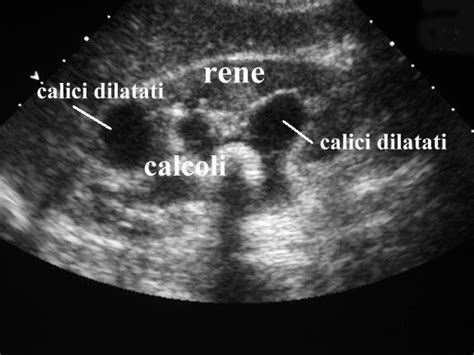

Cause Renali: I microcalcoli renali, come riscontrati nel caso di Anna, una ricercatrice universitaria al settimo mese di gravidanza, possono causare coliche renali. Queste si manifestano con dolori crampiformi intensi, localizzati al fianco, irradiati all'inguine e alla schiena, spesso accompagnati da nausea e vomito. L'ecografia renale è uno strumento diagnostico fondamentale per identificare la presenza di calcoli.

Le infezioni delle vie urinarie (IVU) sono più frequenti in gravidanza e possono estendersi ai reni, causando pielonefrite. I sintomi includono dolore al fianco, febbre, brividi e dolore durante la minzione. La corretta gestione delle IVU con antibiotici è cruciale per prevenire complicazioni.

- Ecografia pelvica e addominale: Per visualizzare l'utero, le ovaie, le tube e gli altri organi addominali, e per escludere una gravidanza ectopica o altre anomalie.

- Esami delle urine e urinocoltura: Per diagnosticare infezioni delle vie urinarie.